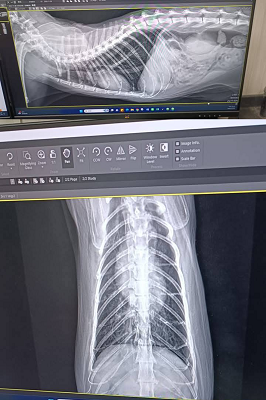

原本是先讓乖豹再留在台北安養之家觀察一小段時間,希望確定健康無虞後,再讓他回到熟悉的大湖安養之家,但在2021年1月,照護員回報乖豹食慾體重都有漸降,1月23日呼吸看來急促,立刻約診沐恩醫院檢查,檢查結果,體溫40.3度,超音波及X光檢查發現胸腔有不明團塊及胸水,給予鎮定後抽出了有膿的胸水,當天辦理住院打泰寧抗生素針,醫師研判是嚴重的細菌感染和發炎造成膿胸,住院2天時,紅血球有持續降低的情況,血容比低到21,1月25日放置胸管引流、沖洗胸腔並引流膿水,每日都需要血檢及沖洗胸腔,在狀況嚴重會需要開胸手術移除胸腔中的膿包及清創,可能會需要輸血,幸好乖豹的食慾精神都有逐漸變好、血容比也有慢慢回升,至2月4日胸管沖洗出都已是乾淨的水,食慾精神也都穩定,醫師認為已可出院自行照護醫療,因治療剃掉肚子一大片毛的乖豹,讓大家很心疼,怕他冷為他穿上可愛又保暖的衣服,也每天準備好多好吃的罐罐幫他補身體,至2月17日回診的X光檢查,原本住院時胸腔有一大一小兩個團塊已經都不見了,這樣表示大團塊只是膿包,所以吃了抗生素就消失了,3月17日再回診,血檢結果都有很好的進步,體重也有回升,膿胸的危機已經解除,只要三個月後再回診拍X光及追蹤血檢即可。

原安置於苗栗貓屋的乖豹於2025年10月與其他貓咪全數移回台北安養之家後發現體型逐漸消瘦,且背上有一顆顆肉瘤以及牙齒有鬆動的狀況,於是安排2025年11月28日於沐恩看診,醫師表示整體狀況還不錯,背上粉瘤為良性,主要是牙結石嚴重,研判體重下滑應與此有關,需盡快安排牙周手術。後再於同年12月17日進行牙周手術,後面的臼齒、2顆下門牙及上顎那一顆不好犬齒都移除,保留下面兩顆犬齒,同時背部腫塊偏良性因此暫不切除。本筆醫助是自2025年11月28日至2025年12月17日間於沐恩醫院的費用,包含看診各項檢驗、牙周手術及用藥。

2025/11/28 乖豹 沐恩看診 林院長

一、看診說明

整體都不錯,主要是牙齒結石嚴重,

盡快安排時間處理,

變瘦很多應跟牙齒有關。